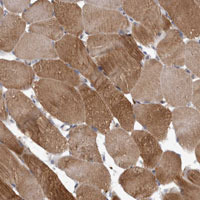

- Experimental details

- Immunohistochemical staining of human skeletal muscle with LOC100130988 polyclonal antibody (Cat # PAB28260) shows moderate cytoplasmic positivity at 1:10-1:20 dilution.

- Validation comment

- Immunohistochemistry (Formalin/PFA-fixed paraffin-embedded sections)